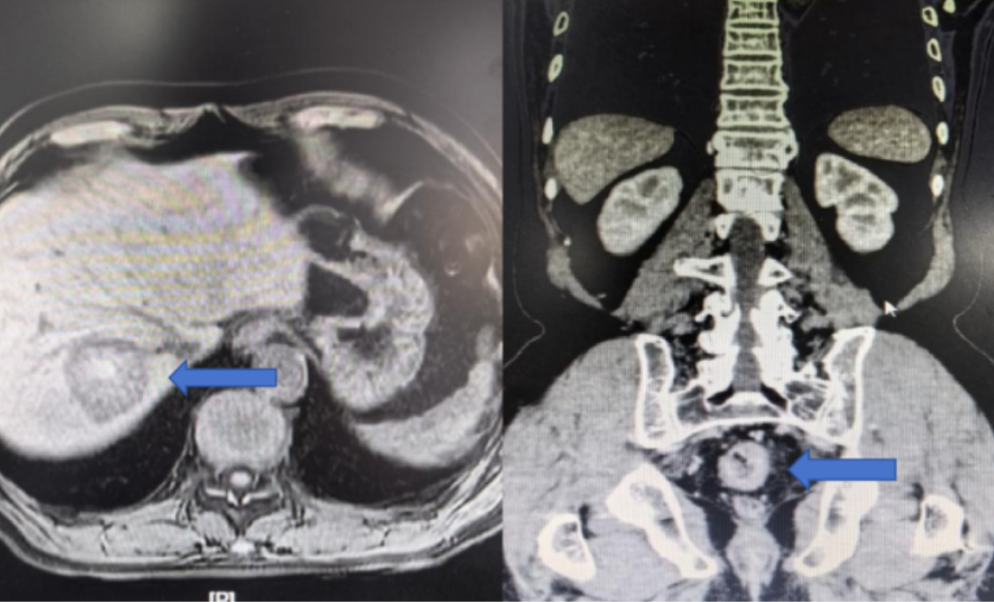

入院后,详尽的术前检查揭示了更为复杂的病情:腹部CT提示肝右叶存在异常高密度灶,高度怀疑为转移瘤并伴出血。肝脏MRI进一步明确了诊断:肝右后叶上段占位,考虑转移瘤并出血等。术前诊断清晰——直肠腺癌合并肝转移。面对这一直肠腺癌合并肝转移的复杂病例,是同时针对同期切除原发病灶与转移灶,还是先实施辅助治疗这一关键诊疗决策,朱利勇教授团队第一时间联合肝胆外科、肿瘤科、麻醉科、临床营养科等多学科专家开展MDT会诊。经过充分讨论与全面评估,专家团队一致认为,同期切除直肠原发病灶和肝脏转移病灶是当前对患者最有利的治疗策略,术后将根据病理结果辅以化疗等综合治疗。